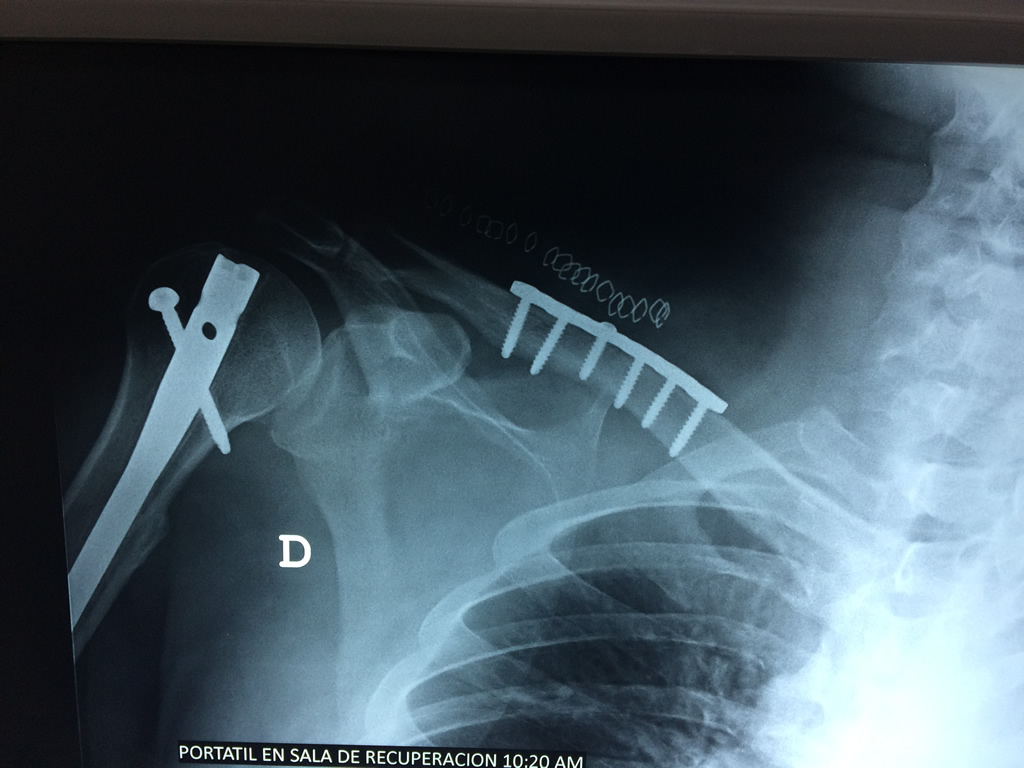

Cirugía de Fémur - Clavícula

La clavícula es un hueso largo, con forma de "S" itálica, situado en la parte anterosuperior del tórax. Junto con la escápula forman la cintura escapular. Se puede palpar por toda su longitud y se extiende del esternón al acromion de la escápula, siguiendo una dirección oblicua lateral y posterior.

Se considera el único medio de unión entre el miembro superior y el tórax. A pesar de su aspecto, similar al de un hueso largo, posee una estructura semejante a la de un hueso plano, ya que carece de epífisis y de diáfisis, lo que la harían entrar dentro de la clasificación de hueso largo. Carece de un canal medular propiamente dicho.